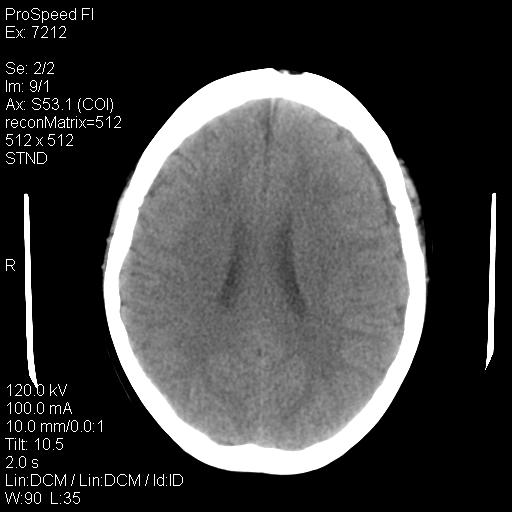

标题: CT18636:F 44Y,头痛三个月,左侧肢体麻木一周。临床诊断, [打印本页]

标题: CT18636:F 44Y,头痛三个月,左侧肢体麻木一周。临床诊断,

右额叶脑沟变浅,脑表面见新月形稍高密度影,考虑慢性硬膜下出血可能。

额顶骨多发穿凿样骨缺损区,不排除骨髓瘤等改变,进一步检查。

额顶骨多发穿凿样骨缺损区,不排除骨髓瘤或嗜酸性肉牙肿等改变,进一步检查。

1)考虑左侧额部慢性硬膜下血肿(或硬膜下积液)。2)颅骨骨髓瘤不排除;建议行进一步检查。

1)考虑左侧额颞部及右侧额部慢性硬膜下血肿(或硬膜下积液)。2)颅骨骨髓瘤不排除;建议行进一步检查。

1)右侧半卵圆中心腔隙性脑梗塞。2)考虑左侧额部慢性硬膜下血肿(或硬膜下积液)。3)颅骨骨髓瘤不排除;建议行进一步检查。